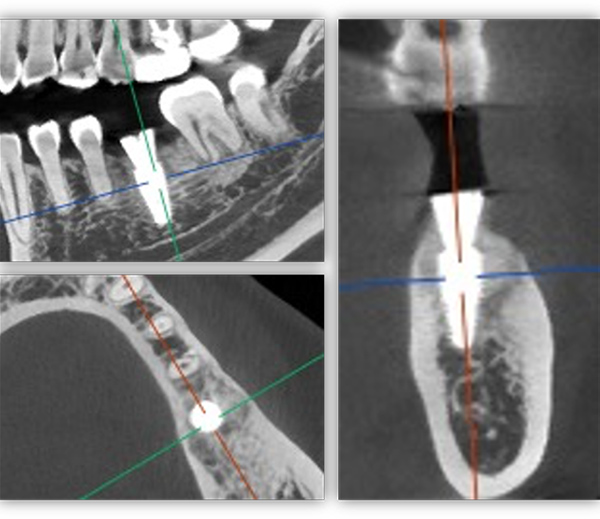

单颗是最常规的种植,不能因为常规就觉得简单,治疗时要追求小而精。从适应证把握到术式选择,再到修复方式,术后的结果有没有达到术前预期效果,都需要用心设计,事后复盘。这位患者是一位来自外地的年轻老师,有一颗6号牙需要种植。她只有在暑假两个月的时间内可以来院,希望能在暑假期间完成治疗。

为满足患者的需求,我为她制订了一个即拔即种、种植后早期负重的方案,把五个治疗步骤缩减为三步。首次来院时,我为她完成了拔牙、种牙和安装基台,6周后来院拆线和取模,两周后完成牙冠修复,也就是戴牙。整个治疗周期仅8周,不到两个月就完成了。

6号牙也就是第一磨牙,是最早萌出的恒牙,比较容易龋坏。它虽然不在前牙美学区,不太容易影响容貌,但出于对美学的高要求,我在设计方案时也考虑了是按常规流程先拔牙,再备洞,还是以修复为导向,先按现有的牙冠来确定未来修复体的形状,再去反推种植体植入的位置。后者对医生来说难度更高一些,但更有利于复原天然牙的形态。

为保证这个方案的顺利实施,我通过查阅文献去印证方案的可行性,还为她建议了适合的种植体,原来三个月的骨结合时间能缩短为两个月,种植体功不可没。